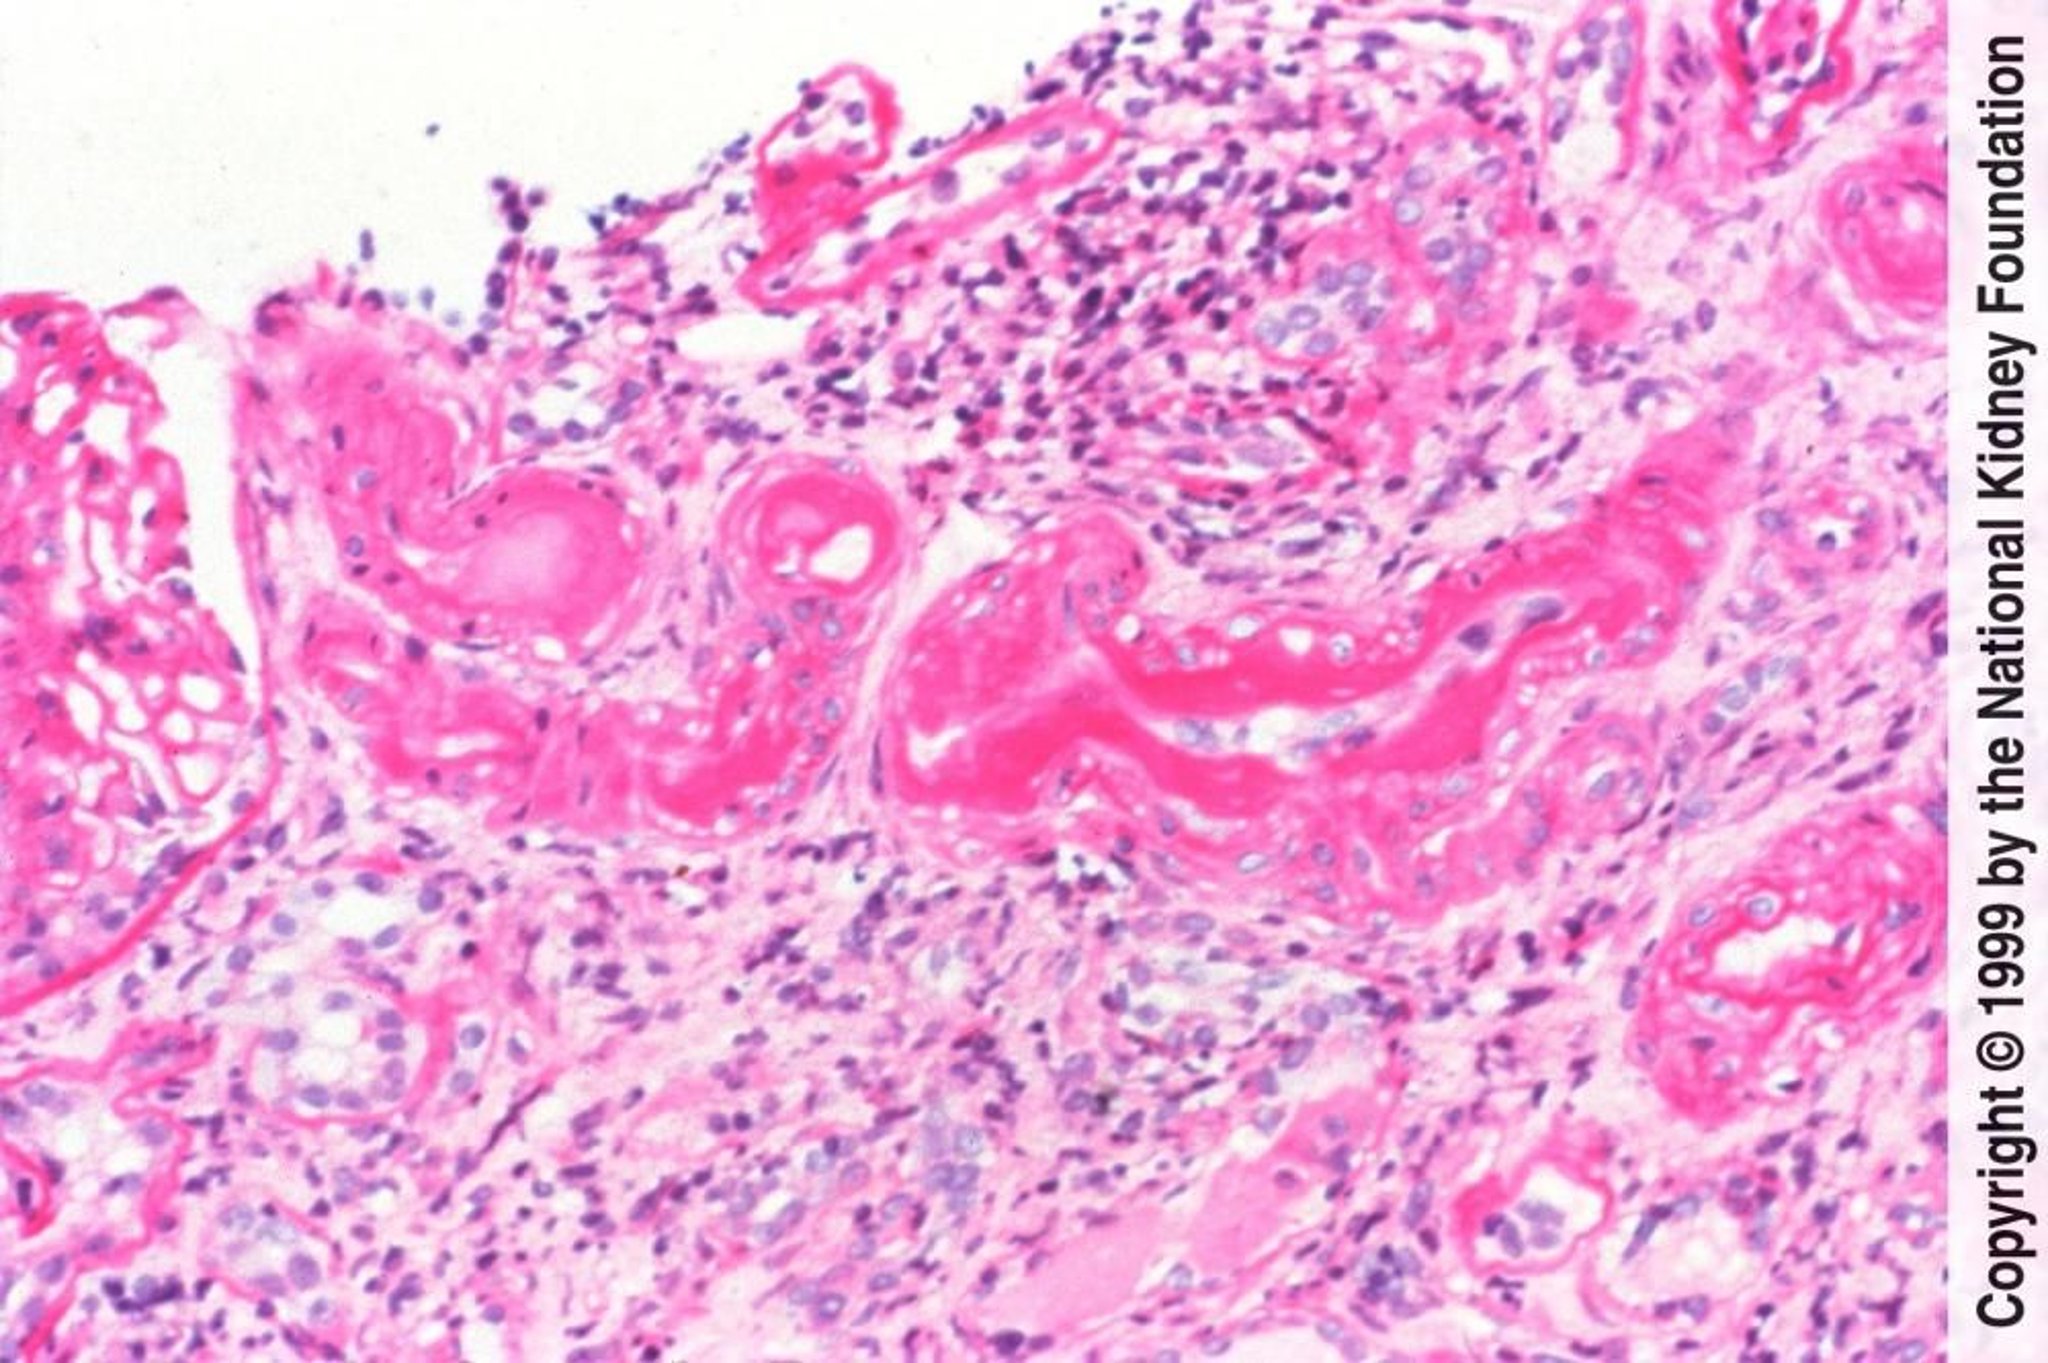

良性高血圧性細動脈腎硬化症の組織学的特徴は,血漿タンパク質の滲出に起因する細動脈の硝子様変性,ならびに血管平滑筋細胞の肥大および過形成の両方に起因する中膜肥厚である(PAS染色,200倍)。

Image provided by Agnes Fogo, MD, and the American Journal of Kidney Diseases' Atlas of Renal Pathology (see www.ajkd.org).